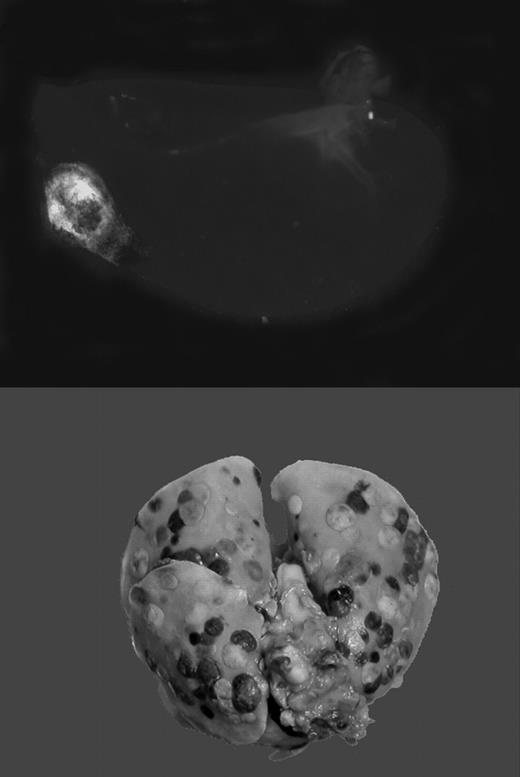

Gαq deficiency dramatically diminishes the metastatic potential of circulating tumor cells. See the complete figure in the article beginning on page 178.